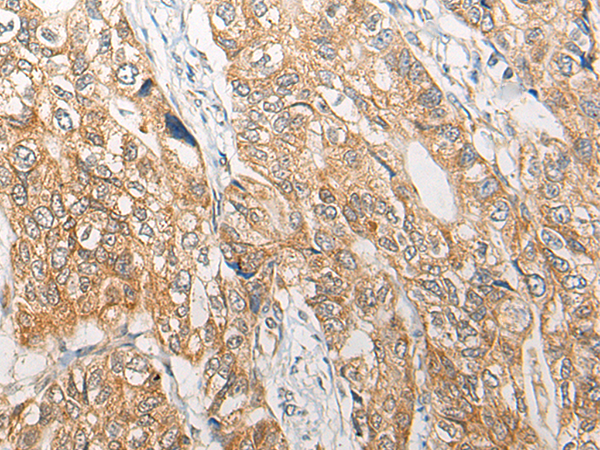

IHC positive control:

Human gastric cancer

IHC Recommend dilution:

25-100